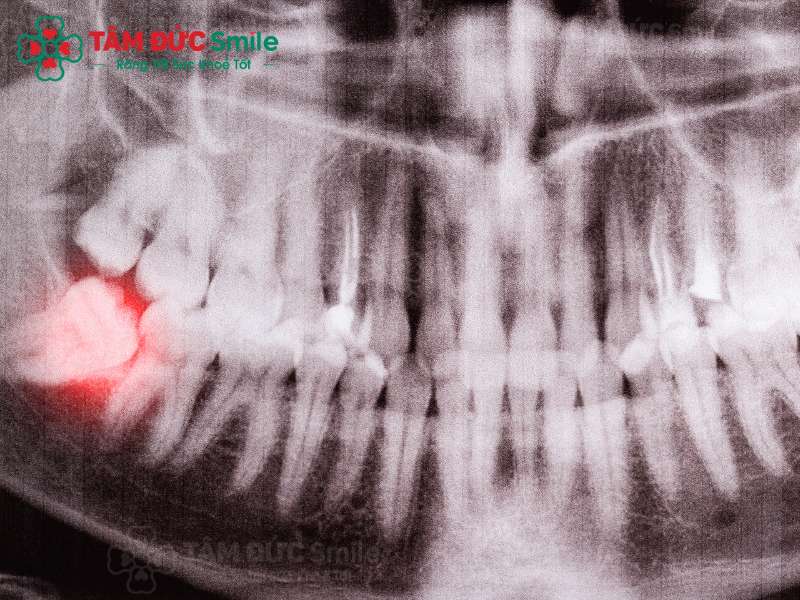

Nguyên nhân chính làm nướu bị sưng trong khi răng khôn mọc là vì răng khôn chỉ mọc một phần. Răng khôn nhô lên một phần trên nướu và sau đó răng khôn mọc lệch, đâm vào kế cận gây viêm nướu. Ngoài ra, còn có những yếu tố khác làm tăng nguy cơ sưng nướu khi mọc răng khôn như:

Răng khôn mọc lệch là một nguyên nhân gây sưng nướu thường gặp

4.5. Giảm sưng nướu do răng khôn mọc bằng cách nhổ bỏ răng khôn

Nếu răng khôn của Quý khách tiếp tục gây viêm nướu kèm theo các vấn đề: Đau nhức, ê buốt… thì nhổ bỏ răng khôn là cần thiết. Bác sĩ sẽ nhổ bỏ răng khôn sau khi đã xem xét cấu trúc răng khôn của Quý khách.

Nhổ răng khôn là kỹ thuật nha khoa phức tạp, đòi hỏi bác sĩ phải có kinh nghiệm lâu năm. Quý khách hãy lựa chọn nha khoa uy tín để nhổ răng khôn, tránh các biến chứng sau này.